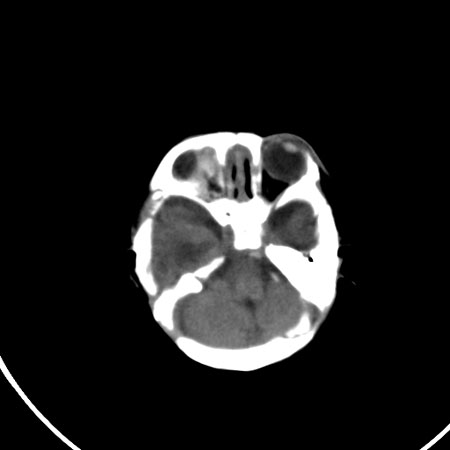

以下是引用小初学者在2009-1-10 17:51:00的发言:[br]考虑缺血缺氧性脑病后遗性改变。

以下是引用拾荒者在2009-1-10 19:23:00的发言:[br]生后有蛛网膜下腔出血病史,现幕上脑室明显扩张,脑室周围白质局限性密度减低,考虑hie脑病后遗表现。